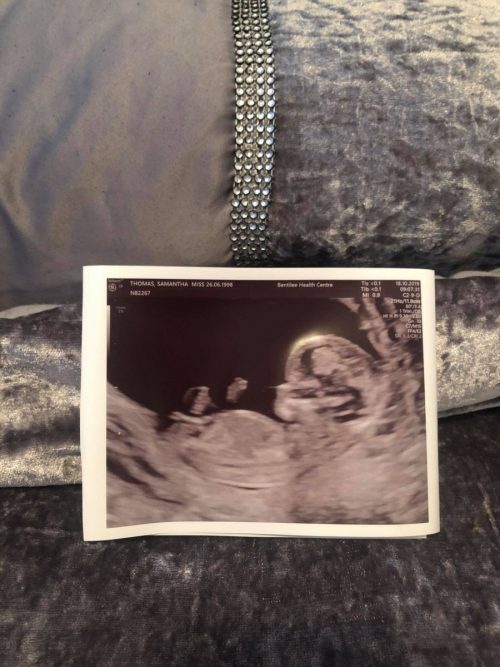

Enseguida, un mar de ilusiones y sueños se apoderan de nosotros y no vemos el día en que podamos abrazar a nuestro bebé. Era lo que pasaba por la mente de la a futura madre de 21 años de edad, Samantha Thomas, de Meir, Staffordshire (Inglaterra).

Todos aseguraron que Sammy “contaba los días para conocer a su hija”, Zara. Sin embargo, el destino la sorprendió con una tragedia arrebatándole la vida sin siquiera poder abrazarla, algo que tanto esperó. Cuando estaba a pocas semanas de dar a luz, de pronto empezó con dolores en el pecho. Aunque vivía con su pareja y padre de la pequeña, Patrick Ratcliffe, en ese momento estaba sola.